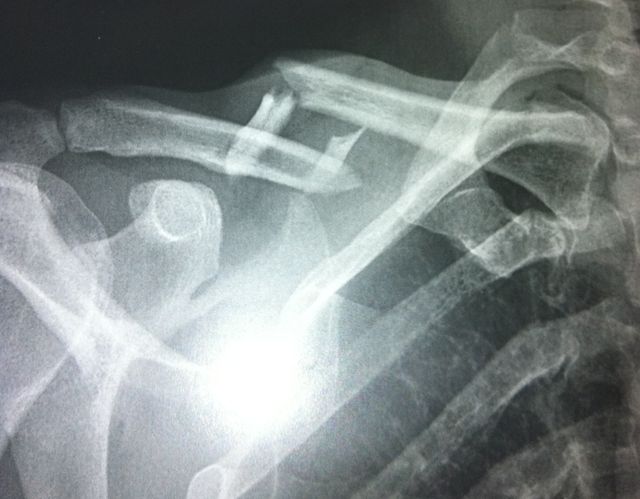

fracture de la clavicule

Figure 3 : Fracture de la clavicule